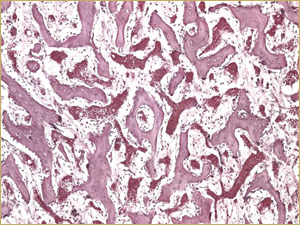

By 8 weeks, all of the sinuses appeared histologically similar (Figs. 7–10). The mature lamellar bone that had been grafted in the autogenous bone group had been remodelled and was no longer present. Similarly, the numerous small-diameter woven bony trabeculae seen at 2 weeks in the BMP groups were no longer present. The sinuses all contained mature, small-diameter lamellar bony trabeculae. No qualitative histologic differences were apparent among the 5 treatment groups at 8 weeks (Figs. 7–10).

Figure 8: Low-power histologic examination of rabbit maxillary sinus augmented with demineralized bone matrix at 8 weeks after procedure. H&E stain, 100× magnification.

No qualitative differences were observed between autografts and DBM bioimplants at 8 weeks. Bone remodelling had taken place, the woven bone that was in contact with the graft particles had converted into lamellar trabeculae, and the stroma had changed into fatty marrow. The differences between BMP implants and non-BMP implants observed at 2 weeks had disappeared by 8 weeks.